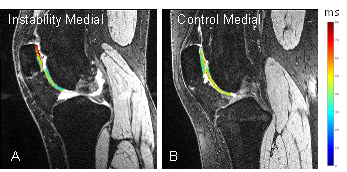

Optimizing Non-Contrast Magnetic Resonance Imaging (MRI) Sequences for Knee Synovitis

PI: Ceylan Colak, MD and Richard Lartey, PhD

Co-I:Zhenzhou Wu, MD; Carl Winalski, MD; Xiaojuan Li, PhD; Elaine Husni, MD, MPH; Joshua Polster, MD; Michael Forney, MD; MacKenzie Dunlap; Katherine Murphy; Erika Schneider, MD

Funding Resource: PAMI Pilot

Abstract:

Inflammatory arthritis (IA) is a group of diseases that includes rheumatoid arthritis (RA), psoriatic arthritis (PsA), and ankylosing spondylitis (AS). Joints with IA often have proliferative, hyperplastic synovitis that can cause significant cartilage loss, bone erosion that can lead to progressive physical disability. Proliferative synovitis is an important indicator of disease activity since it drives the inflammatory processes. Imaging plays a key role in diagnosis and measurement of disease burden and treatment response. While radiography and ultrasound are very useful, only magnetic resonance imaging (MRI) provides an overview of the entire joint. Currently, intravenous (IV) contrast is used to visualize synovitis on MRI and differentiate it from joint fluid, and dynamic contrast-enhanced (DCE) MRI is considered the imaging gold standard. Non-contrast MRI techniques, e.g. diffusion-weighted MRI, can assess IA synovitis, however they suffer from low spatial resolution limiting their value for small joints such as the wrist. While cartilage and other joint structures have been extensively studied with MR relaxation time mapping, joint fluid, inflammatory synovitis, and other intra-articular tissues have not been investigated intensively. T1 mapping was recently used to delineate knee synovitis in OA patients. However, there are no published T1 or T2 relaxation time maps for synovitis in patients with knee IA. At 1.5T, we developed a semi-automated segmentation method for quantifying inflamed synovitis using DCE MRI. We propose to optimize the acquisition parameters of non-contrast 3D FSE (3D SPACE) for the robust clinical evaluation of inflammatory synovitis.